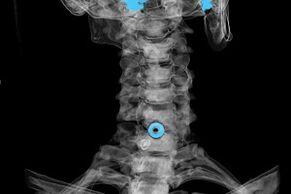

The diagnosis is based on characteristic symptoms, but also used:

- X-rays.The method is ineffective, especially in the last stages of the development of osteochondrosis.

- MRI (magnetic resonance imaging) of the cervical spine.A method that allows you to see bone structures, ruptured intervertebral discs, their size and direction of development.

- Computed tomography.A less effective solution than MRI because it is difficult to determine the presence and size of hernias.